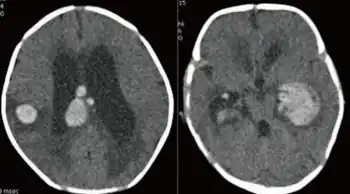

Symptoms may differ greatly, as apparently modifiers control to some degree the amount of FVII that is produced.[1] Some affected individuals have few or no symptoms while others may experience life-threatening bleeding. Typically this bleeding disorder manifests itself as a tendency to easy bruising, nose bleeding, heavy and prolonged menstruation, and excessive bleeding after dental or surgical interventions. Newborns may bleed in the head, from the umbilicus, or excessively after circumcision. Other bleeding can be encountered in the gut, in muscles or joints, or the brain. Hematuria may occur.

IVH in both lateral ventricles with hydrocephalus and ICH with perilesional edema in the right parietotemporal lobe